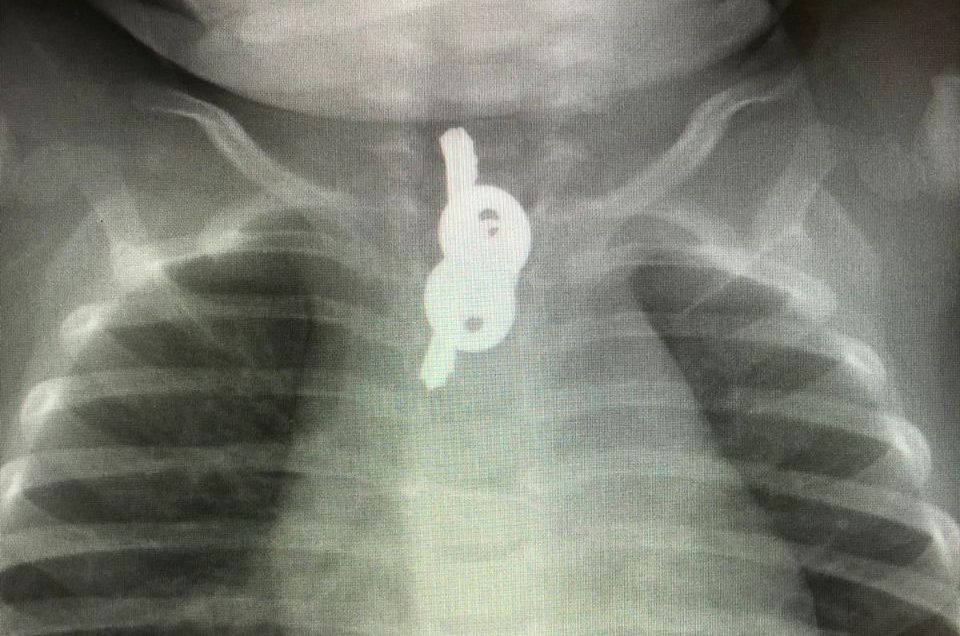

משיחה עם ההורים עולה, כי במשך מספר ימים סבל הפעוט משיעול ומחום לסירוגין ולא היה כהרגלו, טופל בקופת חולים ולא הועלה חשד למשהו חריג. לאחר שהחום שפיתח עלה שוב, החליטו ההורים לפנות למרפאת "טרם", שם בוצע צילום חזה בחשד לדלקת ריאות. ההפתעה שציפתה להורים הייתה גדולה מאוד. בצילום נראו זוג מפתחות בוושט בגובה החזה. התינוק הובהל מידית למרכז הרפואי שערי צדק ושם כאמור הוצאו המפתחות ללא נזק.

ד"ר אוהד כהן, רופא אף אוזן גרון מהצוות שטיפל בילד מספר: "מיד שהתקבל התינוק ולאחר שאבחנו כי המפתחות תקועים בוושט במשך למעלה משבוע הוא הובהל מיד לחדר ניתוח על מנת להוציאם לפני שייגרם נזק נוסף.

עוד הוסיף: "אני שמח שהצלחנו להוציא את המפתחות ללא סיבוכים. לצערנו, אנחנו נתקלים במקרים רבים של בליעת גופים זרים על ידי תינוקות, אך זוג מפתחות מתכת גדולים יחסית לגילו של הילד במשך זמן ארוך יחסית זה יוצא דופן. אני קורא להורים לשים לב ולהרחיק מפעוטות עצמים קטנים, ובמיוחד סוללות ומגנטים שעלולים להיבלע או להישאף במידה ויש חשד של בליעה או שאיפה, יש לגשת מידית לעזרה רפואית על מנת לאבחן ולטפל במהירות ולמנוע נזקים נוספים".